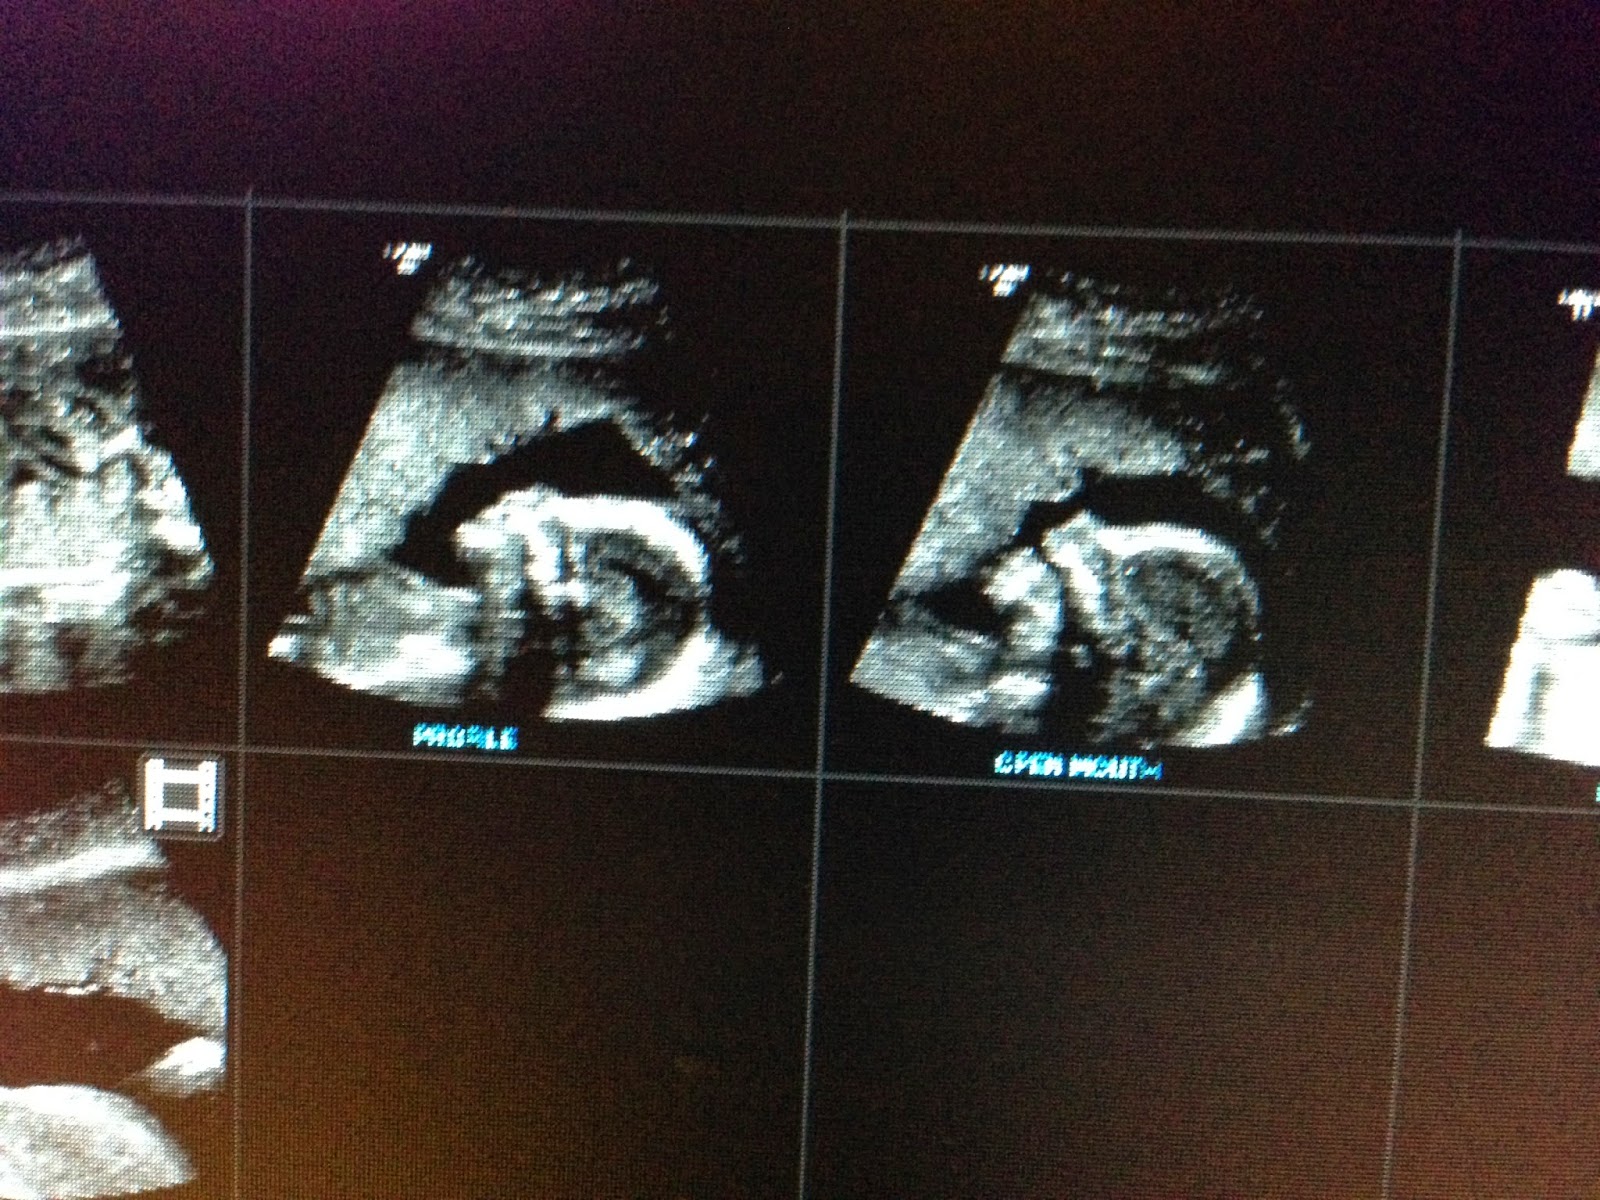

Last highlight of the day was receiving these photos...tomorrow we will be saying he or she

I am so excited to have a new baby in the family.